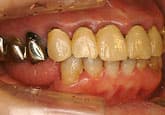

歯の周囲のはぐきや骨が下がって、歯根が露出してくると歯が長くみえるようになります。その状態を歯肉退縮といいます。歯周病が進行すると歯を支える骨が下がって、歯肉退縮をおこします。歯周病があまりない場合でも、生まれつき歯肉がうすい人は、年齢とともに歯肉退縮をおこしてきます。また、不適切なはみがきの仕方や日常のはぎしり、かみ合わせの不調によっても歯肉退縮はおこります。

歯周病とは、歯垢(プラークすなわち細菌)が歯と歯肉の隙間の歯周ポケットに入り、歯ぐきに炎症を起こすことからはじまります。進行すると歯を支えている骨を溶かしてしまいます。正常な歯周ポケットは1~3mmですが、歯肉の炎症や骨の吸収によって4mm以上に広がります。歯周病になると歯肉が腫れる・出血する・口臭がする等の症状がでて、痛みなどの症状はないまま歯を支えている骨が溶けてきます。進行すると歯がぐらぐら動いてきて、十分にかめなくなります。

歯周病の治療で最も大切なのは『患者さん自身による正しいハミガキ』です。患者さんの頑張り次第で症状は良くなりますし、うまくみがいてくれないと、改善せず、悪化することもあります。治療は、患者さんと歯科医師・歯科衛生士が連携することで進めていきます。その上でまず徹底した歯石除去を行います。その後、再度検査を行い、その結果によって、個々の患者様にあった治療計画を作成します。症状が進行していて、適応症であれば、症状に応じて歯の周囲の骨や歯周組織の再生治療を行ったり、歯周ポケットの除去療法を行ったりします。また、審美性の改善やはみがきをしやすくするために、歯肉の移植処置などを行う場合もあります。